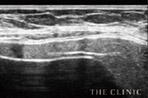

冒頭でも触れたように、シリコンバッグプロテーゼ(豊胸インプラント)は人工物なので、破損のリスクから延々と逃れることは不可能です。しかし、破損が引き起こす二次被害を回避する方法はあります。それが、定期的なエコー検査です。

見た目に症状が現れにくいトラブルでも、エコー検査でなら異常が明確に映し出されます。つまり、最悪の状態に至る前にシリコンバッグプロテーゼを除去(抜去)できるのです。バストのボリュームダウンを懸念される方には、ヒアルロン酸豊胸や脂肪注入豊胸でバッグ除去後にボリュームを補う方法もあります。